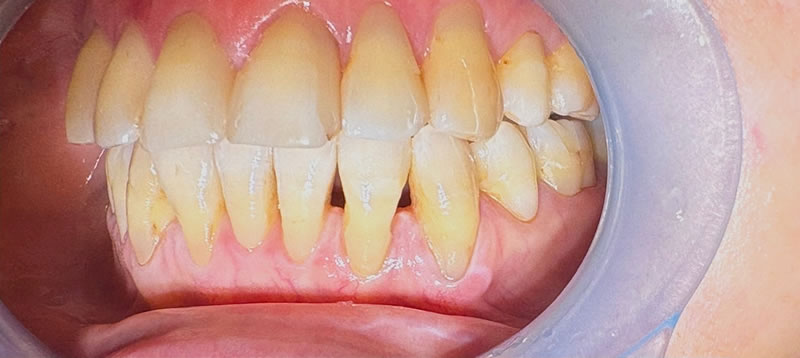

矯正後の60代後半女性で、下の前歯の歯茎下がりの空隙部位に食べものが入ってしまったり唾液が飛ぶから、封鎖したいという主訴でした。

ダイレクトボンディングによる歯の形態修正で足場を作り、ヒアルロン酸をキャリアにした幹細胞由来サイトカインとレーザーによる治癒促進治療による歯周組織再生誘導を同時に併用しました。